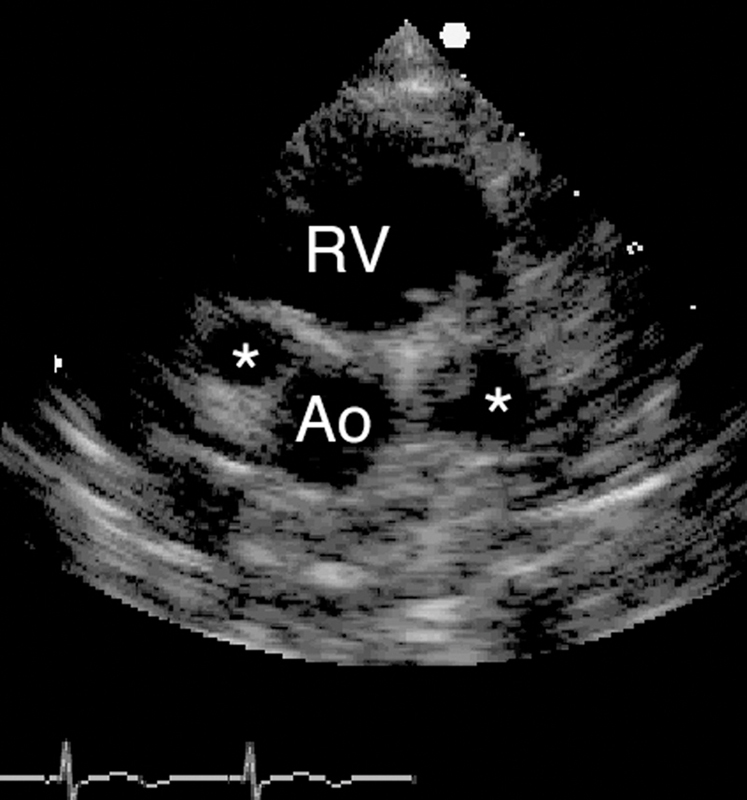

فحوصات تشخيصية لبعض امراض القلب والشرايين التاجية